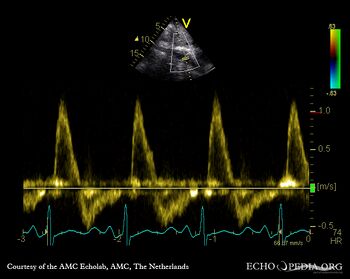

Severe aortic regurgitation

A5CH: Color Doppler signal of severe aortic regurgitation Continuous-wave Doppler signal of severe aortic regurgitation, PHT 135 msec